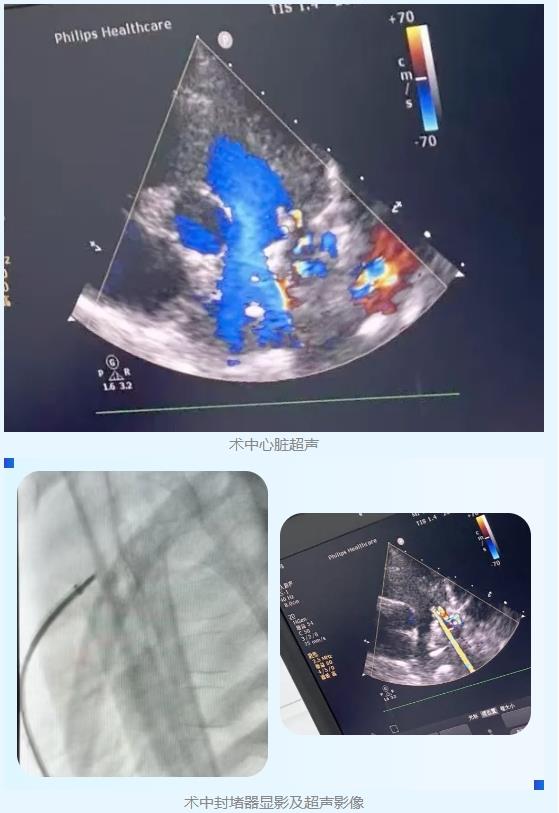

手术在麻醉手术科与超声医学科团队协作下开展,由交大一附院心血管外科成革胜教授带领榆林医院心血管外科医疗团队共同实施。术中团队根据患儿血管走行特点,及时调整手术路径,建立“股动脉-PDA(动脉导管未闭)-股静脉”轨道,手术全程用时20分钟,成功完成封堵手术。为提升手术安全性与术后恢复质量,术中全程在经胸超声监测下完成封堵器选择与封堵器封堵效果的评估,避免使用造影剂及放射线,最大限度降低肾损伤与辐射暴露风险。

术后,医护团队对患儿进行密切监护与康复指导,经复查心脏超声显示,患儿心脏结构与功能恢复良好,已达到出院标准,目前已顺利康复出院。